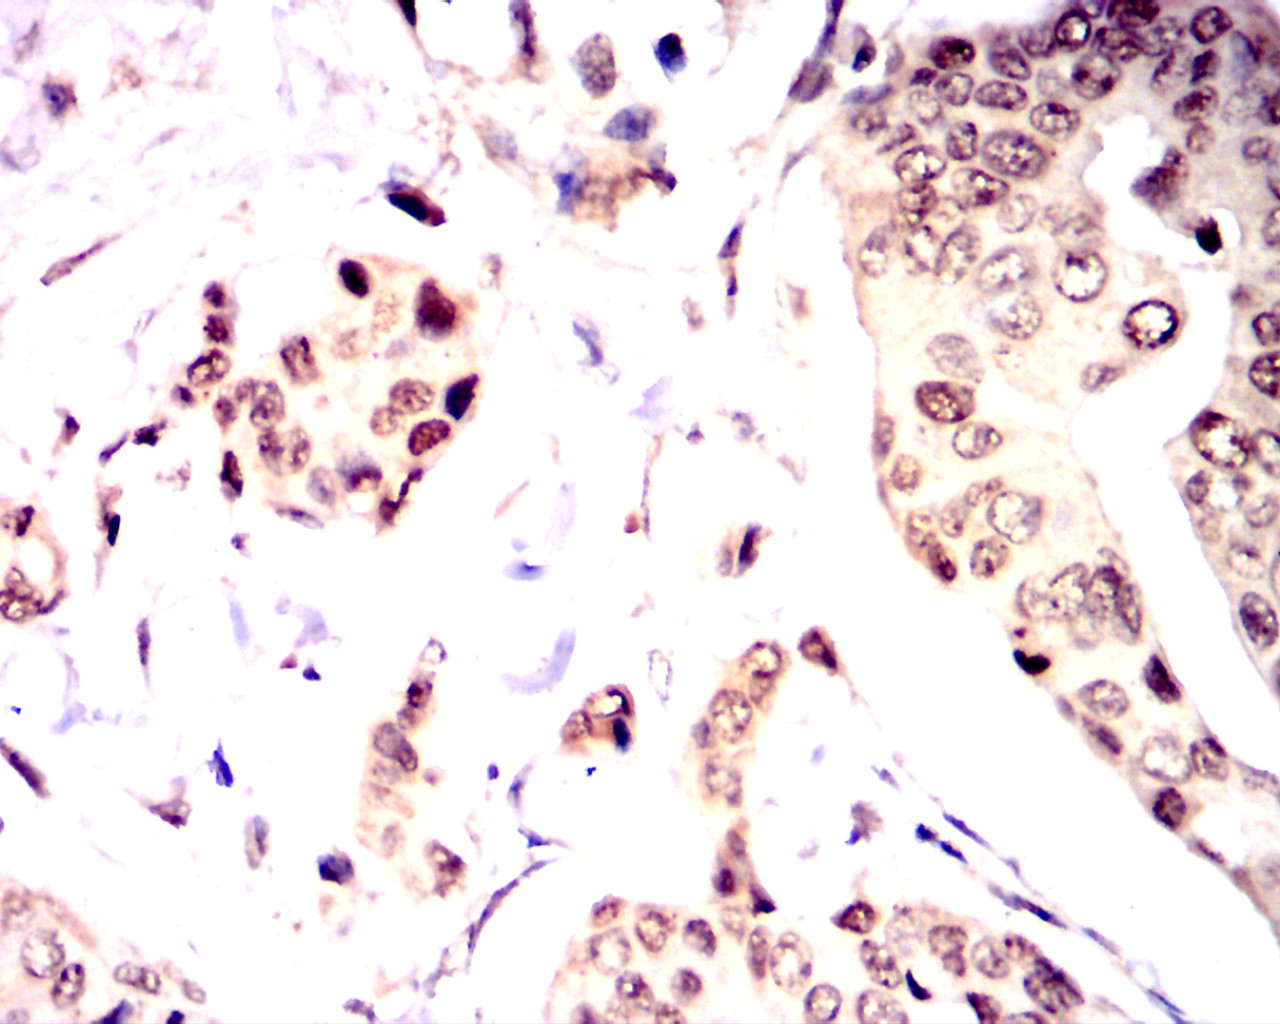

Immunohistochemical analysis of paraffin-embedded breast cancer tissues using OTX2 antibody with DAB staining.Pre-treat the sections with heat-mediated antigen retrieval using sodium citrate buffer (pH 6.0) (OM750020) for 2 minutes. Wash the sections with ddH₂O and PBS (OM750003). Block the tissue with 10% non-immune goat serum(OM760028) at room temperature for 30 minutes. Incubate the tissue with the primary antibody diluted at a ratio of 1:1500 at 4°C overnight. At room temperature, dilute the secondary antibody, Goat Anti-Mouse IgG (H&L) - HRP(OM644366), at a ratio of 1:200 and incubate for one hour. Use DAB(OM760029)as the chromogenic agent. Counterstain the tissue with hematoxylin, and mount the tissue sections with neutral gum.IHC

Immunohistochemical analysis of paraffin-embedded breast cancer tissues using OTX2 antibody with DAB staining.Pre-treat the sections with heat-mediated antigen retrieval using sodium citrate buffer (pH 6.0) (OM750020) for 2 minutes. Wash the sections with ddH₂O and PBS (OM750003). Block the tissue with 10% non-immune goat serum(OM760028) at room temperature for 30 minutes. Incubate the tissue with the primary antibody diluted at a ratio of 1:1500 at 4°C overnight. At room temperature, dilute the secondary antibody, Goat Anti-Mouse IgG (H&L) - HRP(OM644366), at a ratio of 1:200 and incubate for one hour. Use DAB(OM760029)as the chromogenic agent. Counterstain the tissue with hematoxylin, and mount the tissue sections with neutral gum.